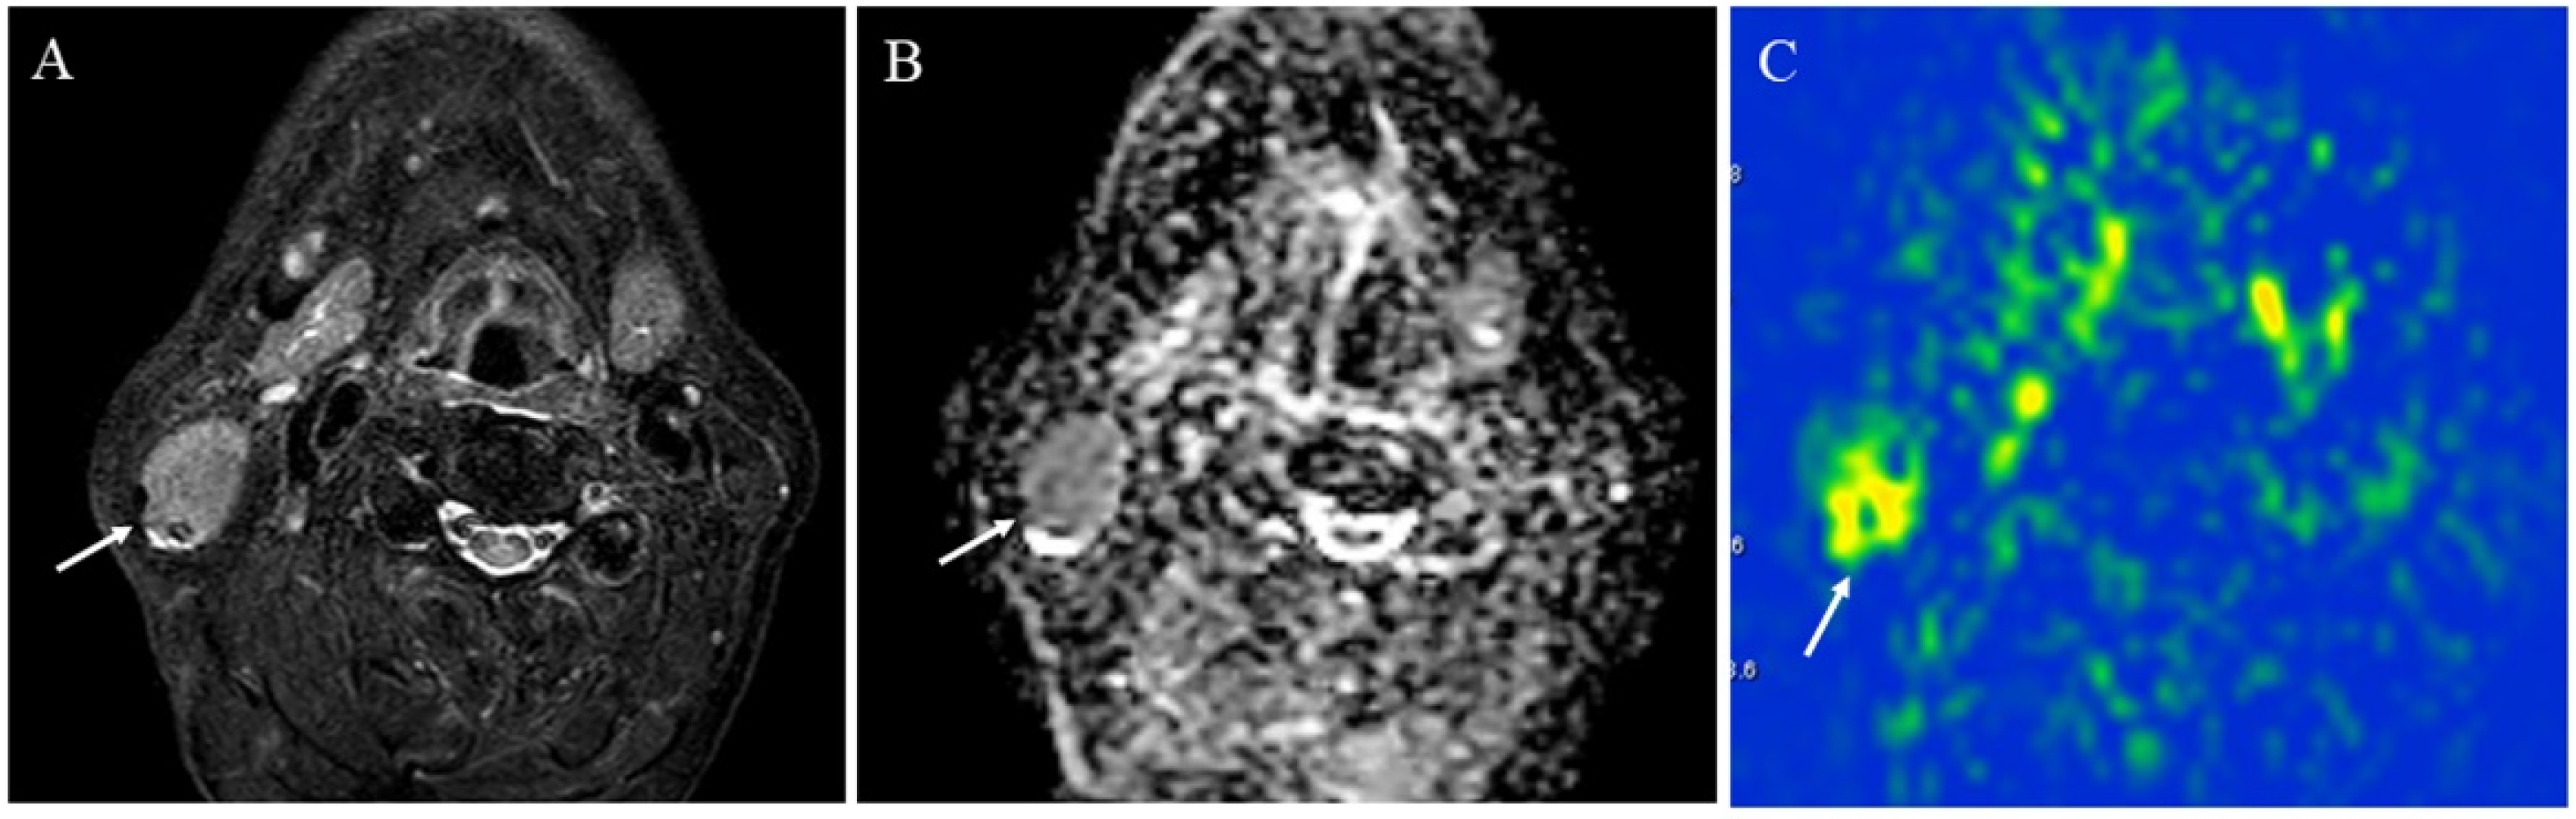

5.1.1. Inflammatory Lesions: Sialadenitis and Dacryoadenitis

5.1.2. Hypervascular Lesions

- Tanaka, F.; Umino, M.; Maeda, M.; Nakayama, R.; Inoue, K.; Kogue, R.; Obara, M.; Sakuma, H. Tumor blood flow and apparent diffusion coefficient histogram analysis for differentiating malignant salivary tumors from pleomorphic adenomas and Warthin’s tumors. Sci. Rep. 2022, 12, 5947. [Google Scholar] [CrossRef]